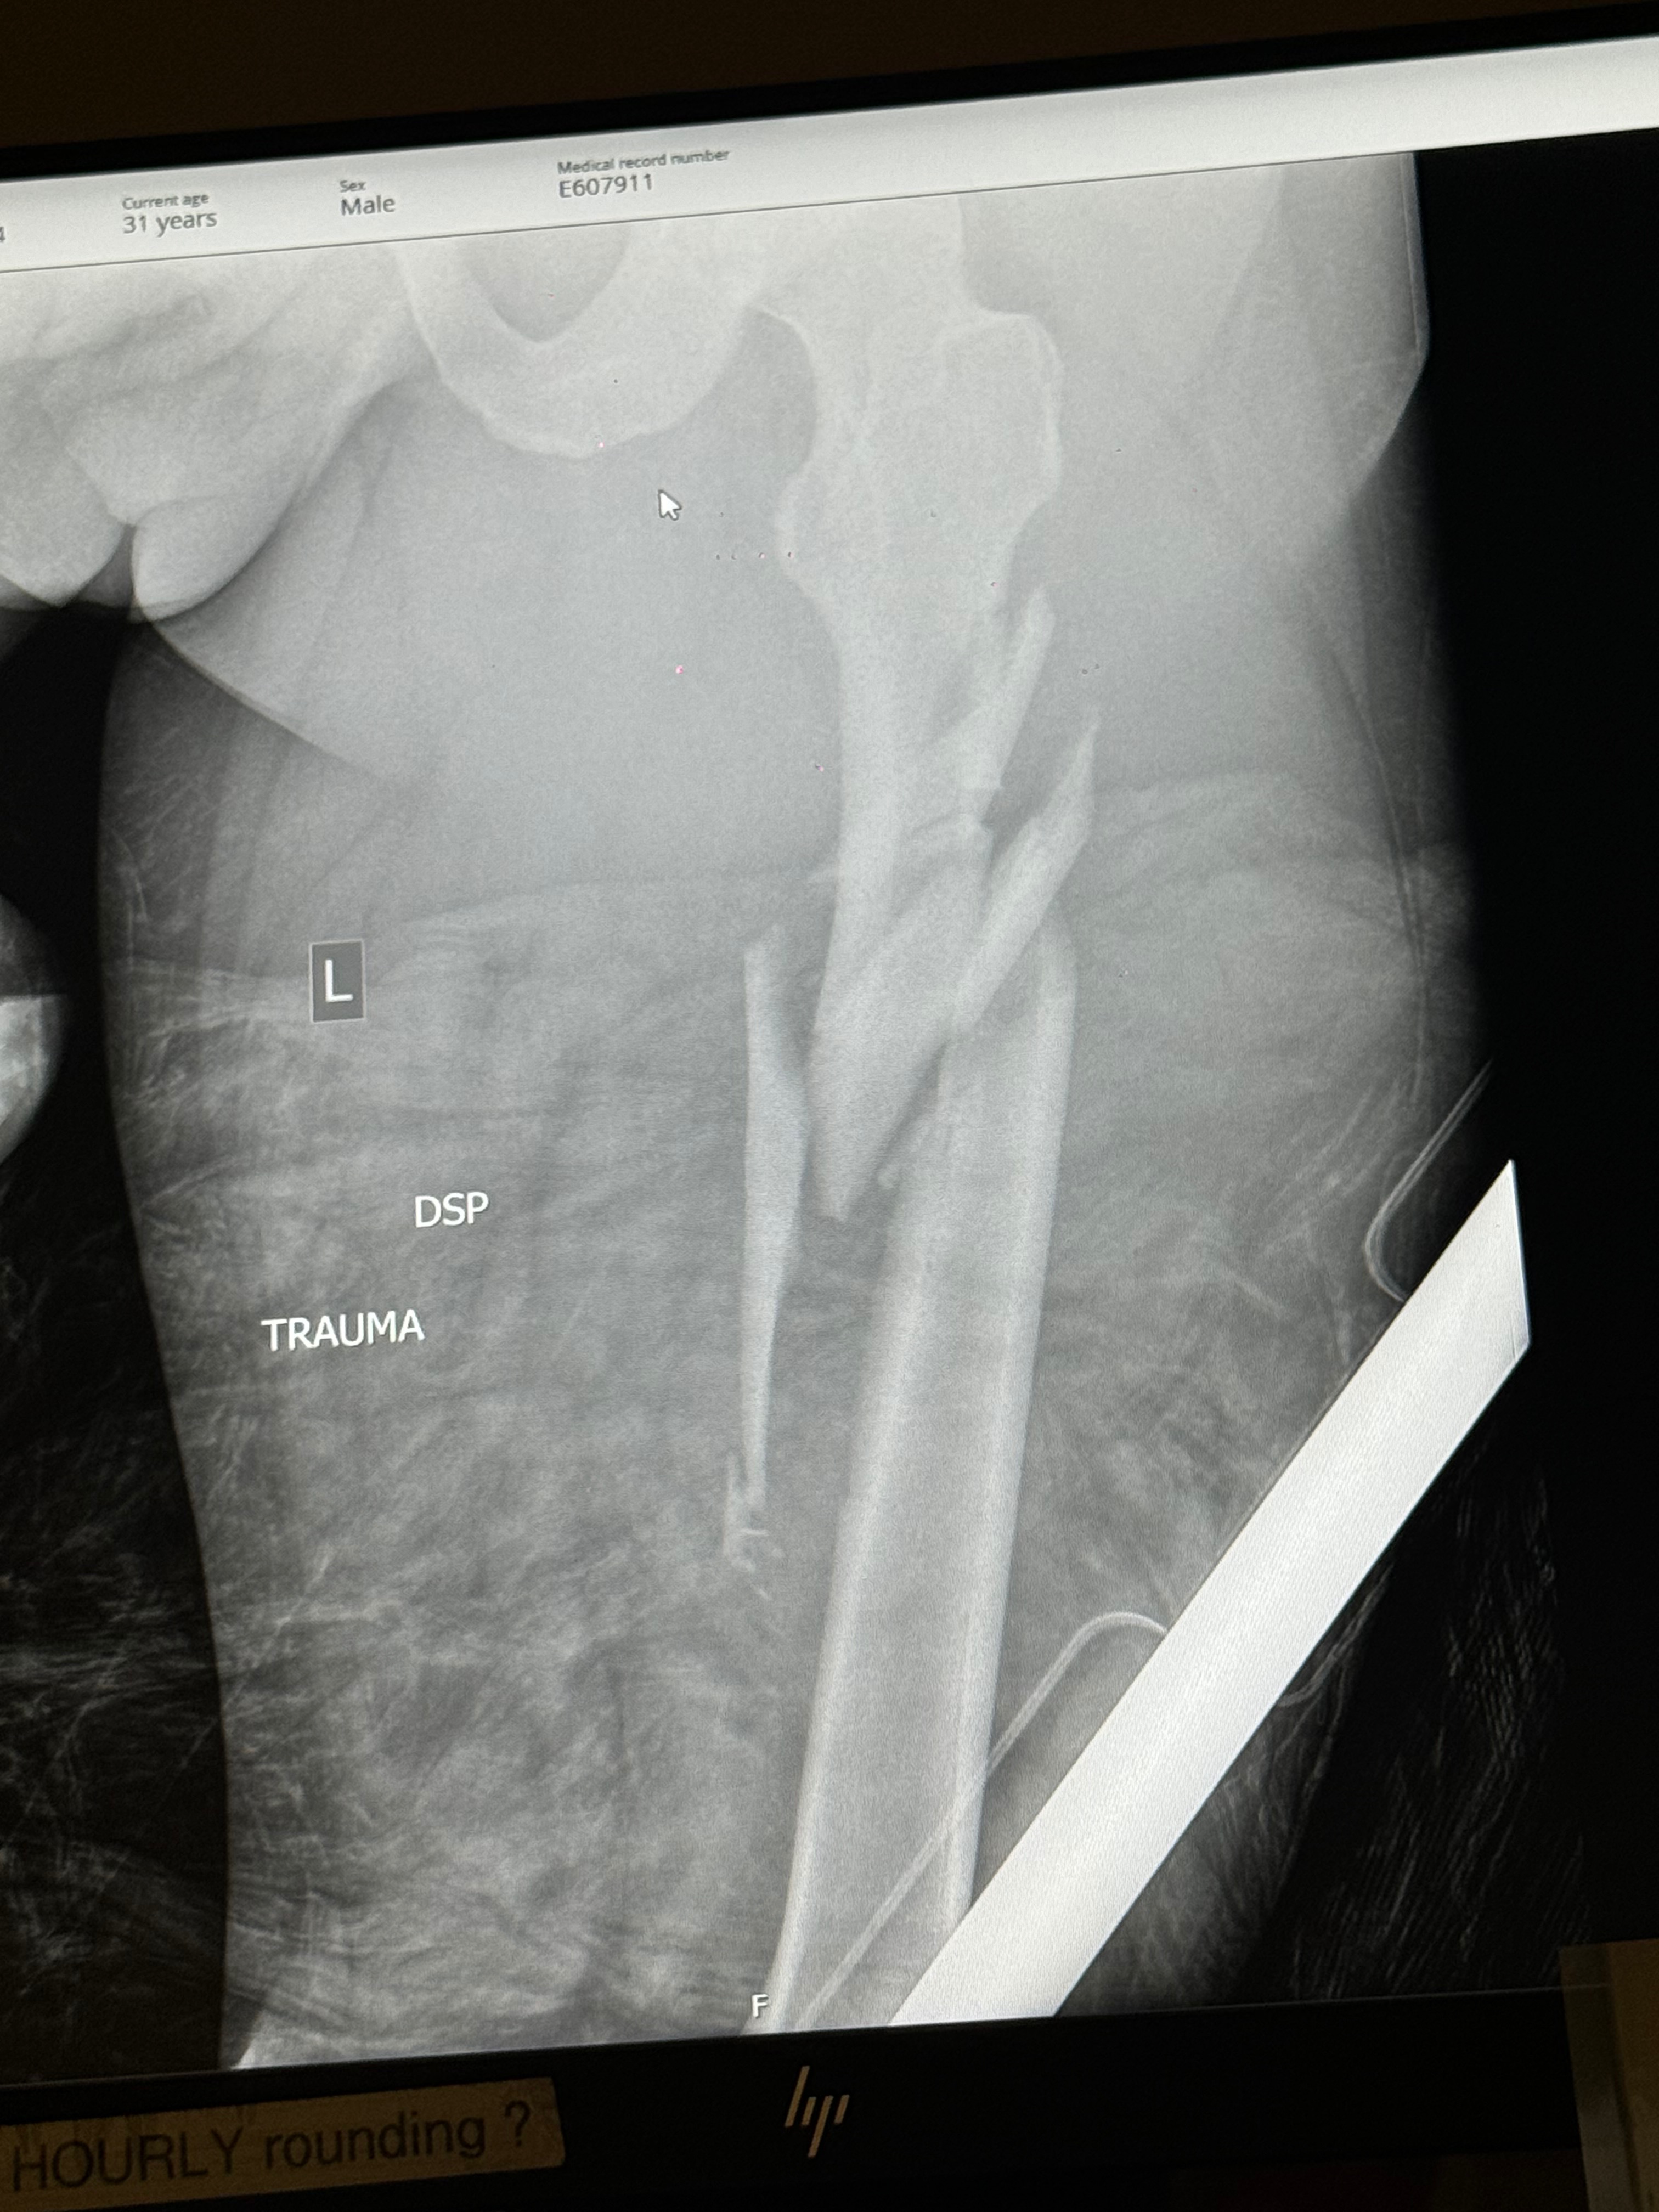

Jorge Castro is a devoted father of two and a talented freelance photographer known for his love of the outdoors and his infectious, bubbly personality. Recently, Jorge’s life changed in an instant when a driver crossed the yellow line on Rahn Rd and hit his car head-on. His four-month-old daughter was in the car with him, but thankfully she was unharmed. Jorge, however, suffered serious injuries, including breaks to both femurs and one ankle. He now faces a long road to recovery and will soon be moved to a rehabilitation facility.